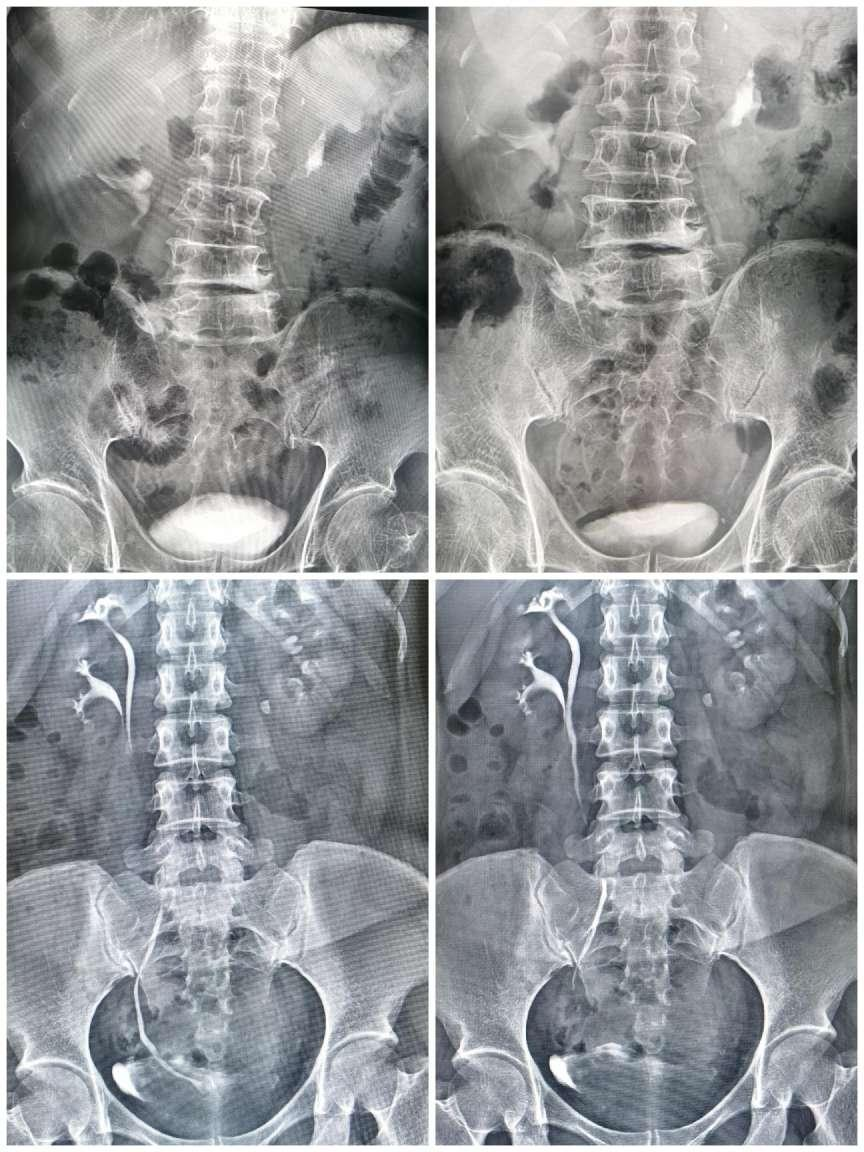

四、脊柱全长摄影及双下肢全长摄影

对脊柱侧弯、髋关节置换、膝关节置换给予全面、直观的影像资料。